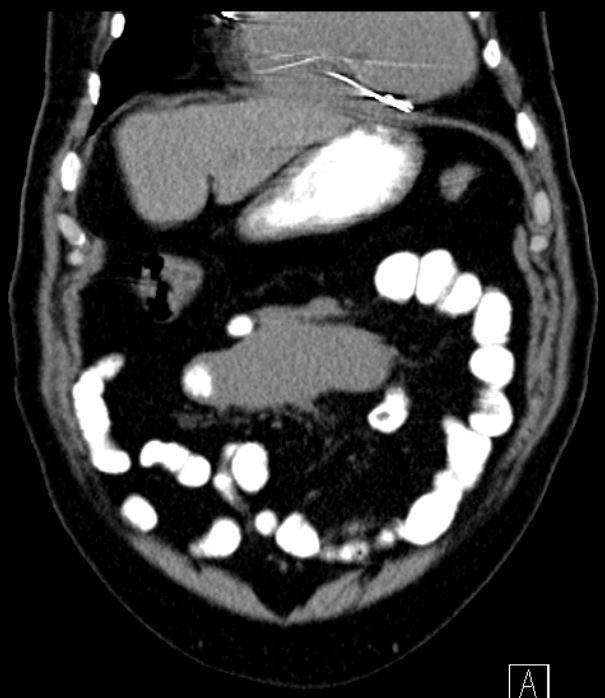

Mesenterialer Bulk |

77-jähriger Mann mit einem abdominalen Tumor und Stenosesymptomatik. Im Dünndarmresektat mit Mesenterialwurzel ein follikuläres Lymphom Grad II-IIIa, FLIPI-Score 2.![]() |